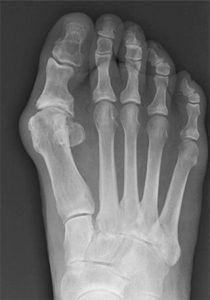

Межфаланговый артроз стопы